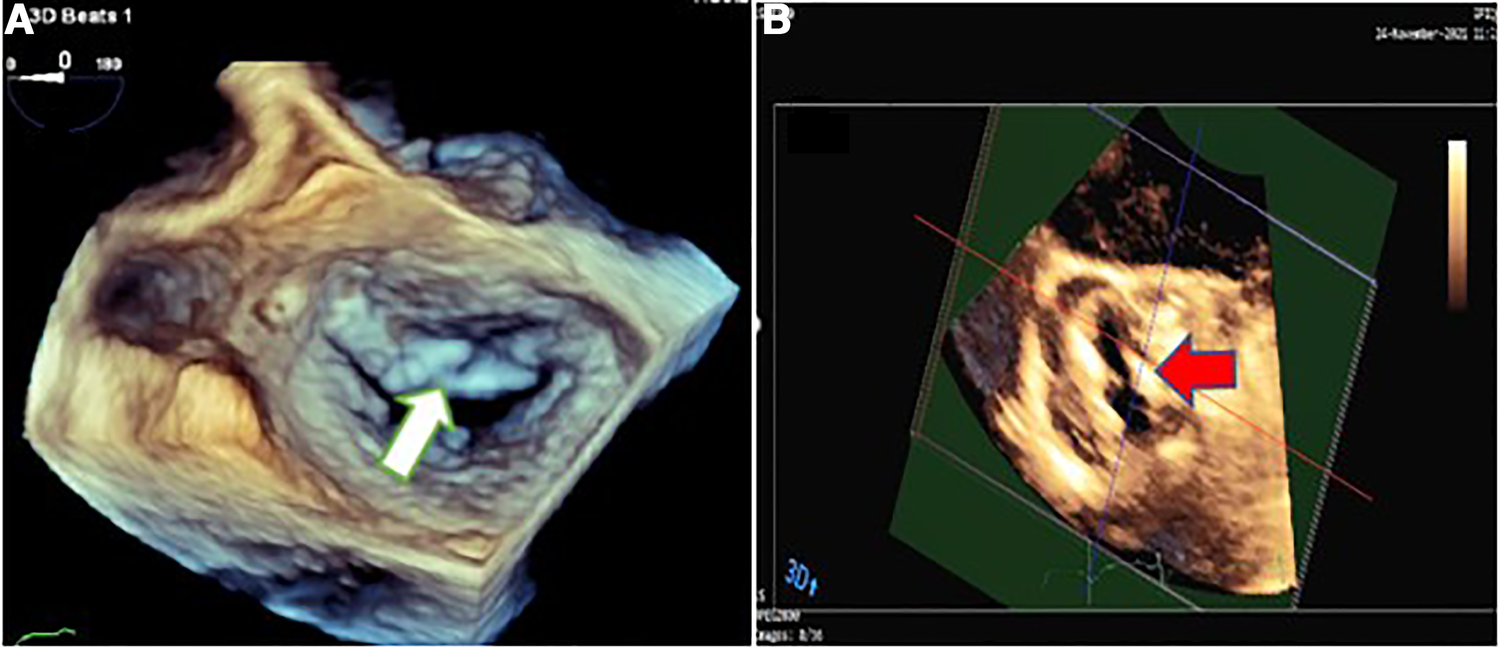

The vegetative lesions on both aortic and mitral valves raised the suspicion of a probable simultaneous coronary artery involvement by IE (Figures 2, 3). Contrast-enhanced chest multidetector CT scan performed showed aneurysmal dilatation of the left main coronary artery (12.7 mm diameter) with an irregular border, originating from the left coronary sinus extending to the proximal LAD artery, suggestive of CAMA (Figure 4). The algorithmic process of diagnosis in the presented case is provided in Supplementary Figure S2.

Figure 3

Three-dimensional transesophageal echocardiography showing mitral valve endocarditis with irregular thickening over the atrial side of the base of anterior mitral valve leaflet (white arrow) (A) and irregularly thickened and destructed bicuspid aortic valve involved by infective endocarditis (red arrow) (B).